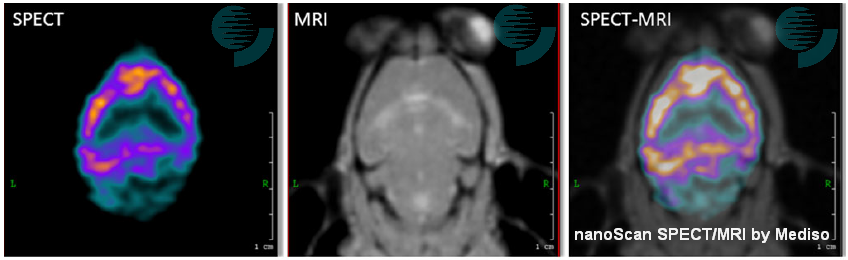

It's an honor to see multi-modality images of PET/MRI and SPECT/MRI acquired by our nanoScan imagers in the article.

A SPECT/MRI application was selected as the image of this blog post. The image shows transverse slices of SPECT and MRI images of a mouse brain. SPECT was acquired using a specific agent for cortical benzodiazepine receptors (123I-NNC13-82431). The lack of anatomical information of SPECT acquisition is complemented with the information provided by MRI, in which the eyes, the olfactory bulbs and the first and second ventricles are shown. The multimodality SPECT/MRI image provides information about functional benzodiazepine receptors from SPECT allied to good soft tissue contrast from the MRI.